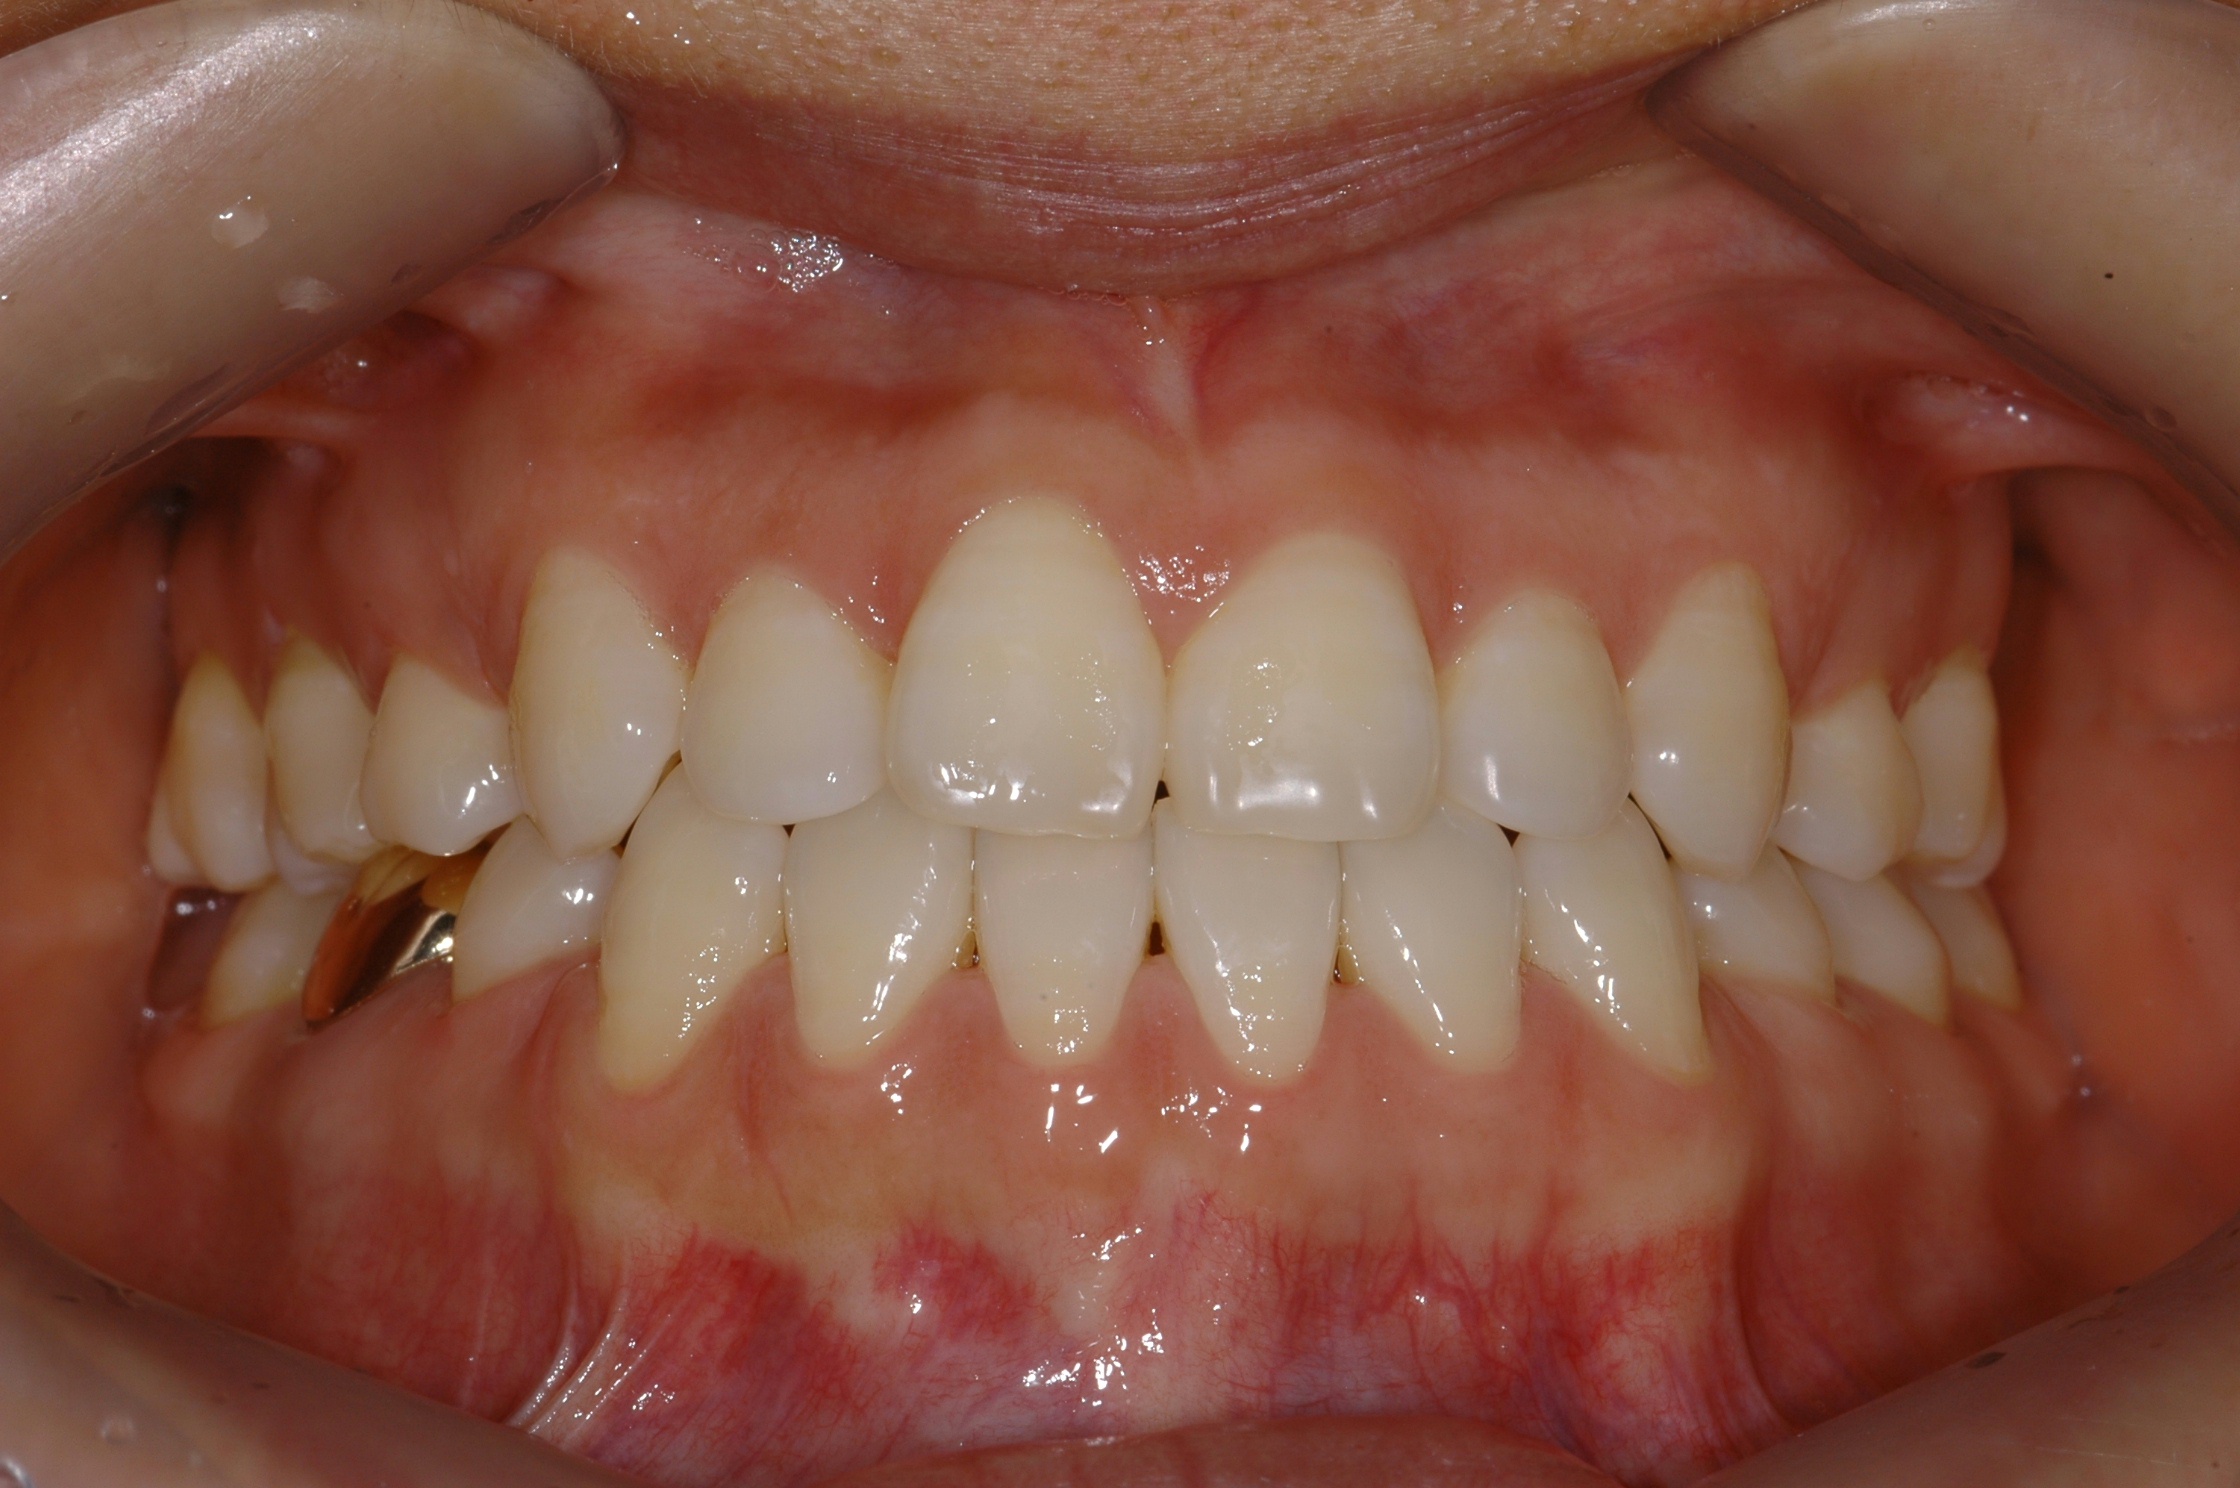

치료 후 사진입니다.